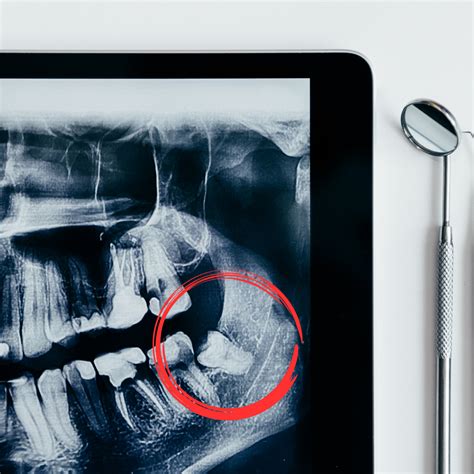

Entonces, ¿por qué la extracción de las muelas del juicio es una de las cirugías dentales más comunes? Si no hay espacio para una muela del juicio, puede quedar impactada, lo que significa que no erupciona por completo de la encía. Según la Asociación Estadounidense de Cirujanos Orales y Maxilofaciales, alrededor del 90% de las personas tienen al menos una muela del juicio impactada, lo que puede provocar caries, acumulación de placa e infección. La extracción de las muelas del juicio puede ayudar a prevenir estos problemas.

Por el contrario, dado que los dientes impactados están atrapados debajo de la línea de las encías o en la mandíbula, no se pueden extraer simplemente con anestesia local. Para extraer una muela del juicio impactada, su dentista o cirujano oral puede necesitar administrarle sedación y luego hacer una incisión en el tejido de las encías para llegar al diente. Como se señaló anteriormente, las extracciones a menudo tienen un precio por diente. Por lo tanto, si solo una de sus muelas del juicio le está causando problemas, costará menos que si le extraen las cuatro.

- El examen inicial y las imágenes: Necesitará una consulta y un conjunto de radiografías panorámicas antes de que su dentista o cirujano oral pueda extraerle los dientes.